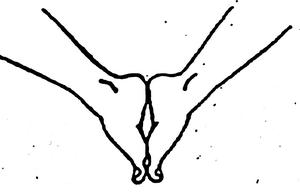

Это упражнения. Например, «гусеничка», или сбор пальцев в кулачок; тяга стопы вовнутрь; упражнения на равновесие. Упражнений для мобилизации мышц стопы много, это тема для отдельной статьи, в будущем обязательно про них напишу больше.